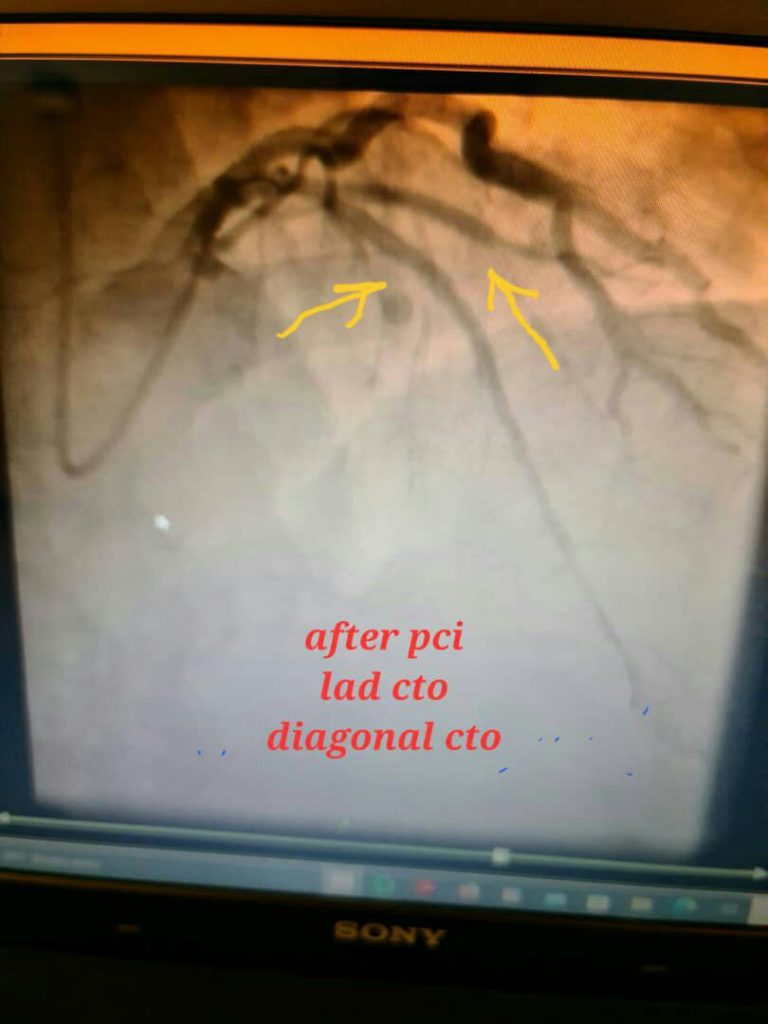

درمان انسداد کامل عروق قلبی بدون نیاز به عمل جراحی باز

آنژیوپلاستی عروق تنگ یا کاملا مسدود قبلی , والووپلاستی